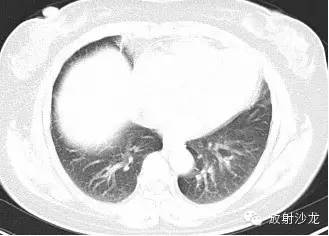

第三例:

51岁男性,体检发现肺门、纵隔、腹腔淋巴结肿大,CT拟诊结节病,后于北京协和医院确诊。

第1—3图显示Garland三联征。第4图显示腹腔淋巴结肿大。